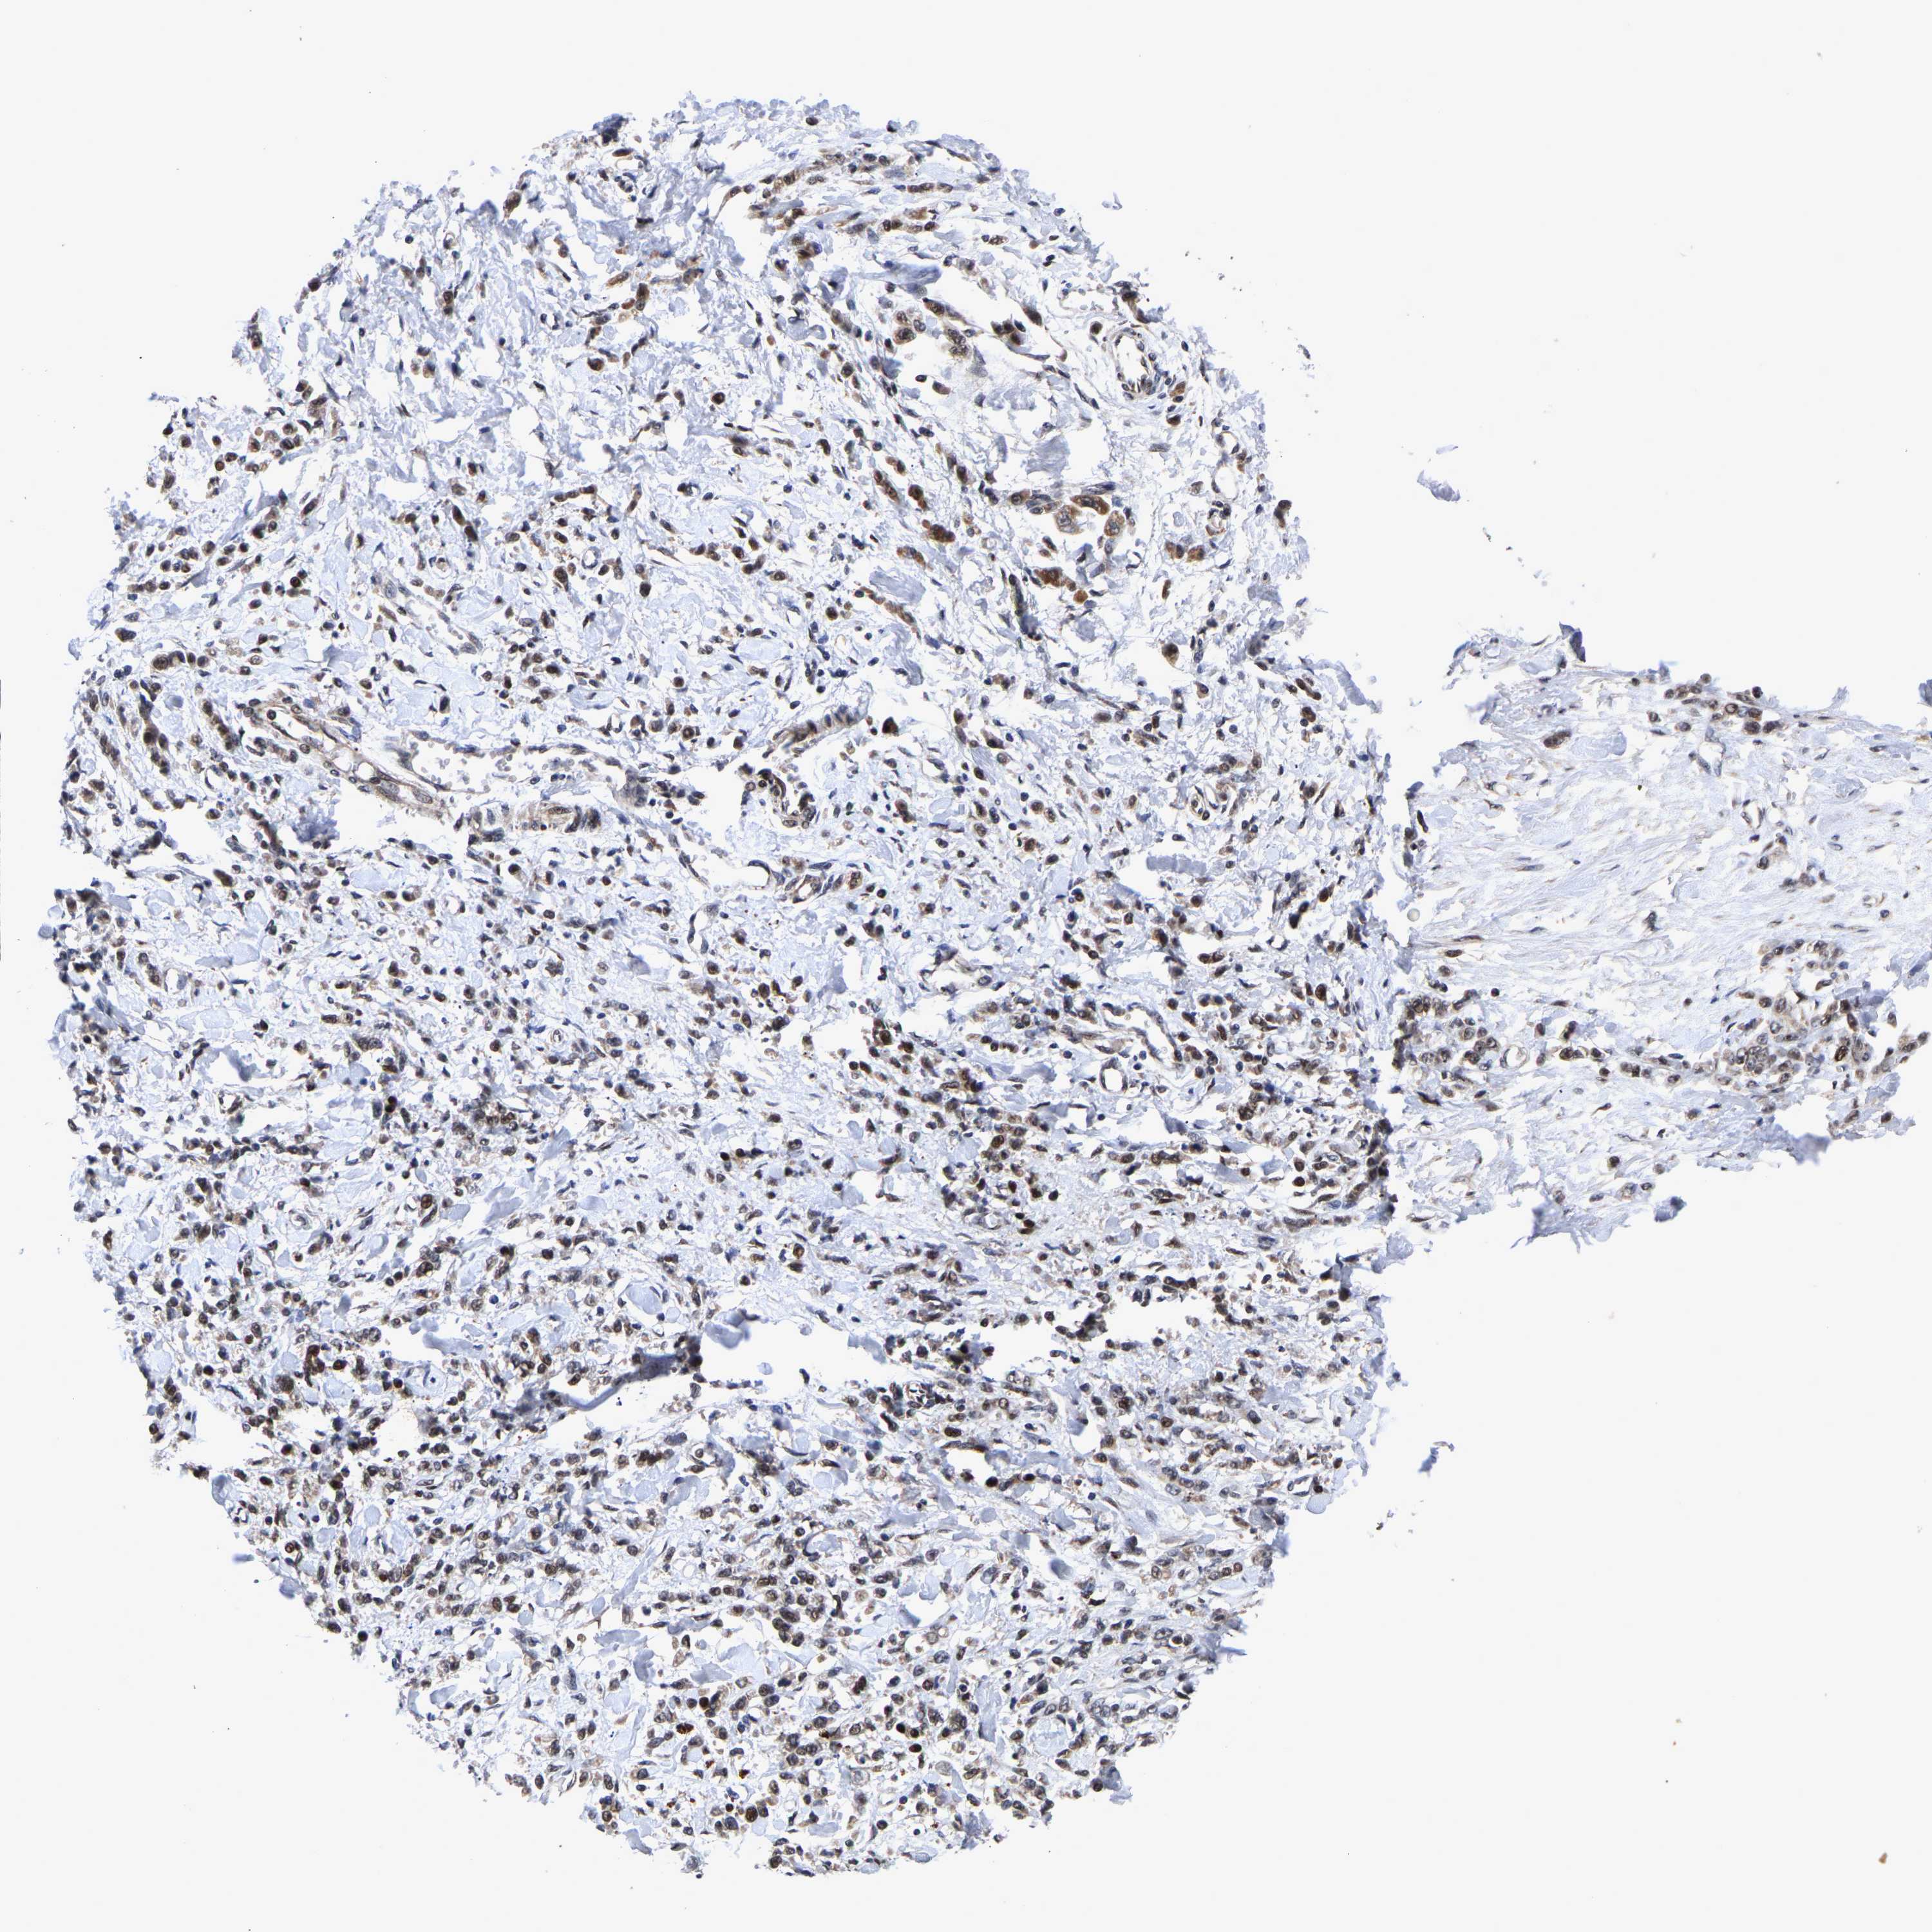

STOMACH CANCER - Protein expressioni

A mouse-over function shows sample information and annotation data. Click on an image to view it in a full screen mode. Samples can be filtered based on level of antibody staining by selecting one or several of the following categories: high, medium, low and not detected. The assay and annotation is described here.

Note that samples used for immunohistochemistry by the Human Protein Atlas do not correspond to samples in the TCGA dataset.

Antibody stainingi

Antibody staining in the annotated cell types in the current human tissue is reported as not detected, low, medium, or high, based on conventional immunohistochemistry profiling in selected tissues. This score is based on the combination of the staining intensity and fraction of stained cells.

Each image is clickable and will lead to virtual microscopy that enables deeper exploration of all samples and also displays staining intensity scores, fraction scores and subcellular localization as well as patient and tissue information for each sample.

Antibody HPA019149

Antibody CAB004464

Staining

High

Medium

Low

Not detected

Intensity

Strong

Moderate

Weak

Negative

Quantity

>75%

75%-25%

<25%

None

Location

Nuclear

Cytoplasmic/membranous

Cytoplasmic/membranous,nuclear

Adenocarcinoma, NOS

Adenocarcinoma, High grade